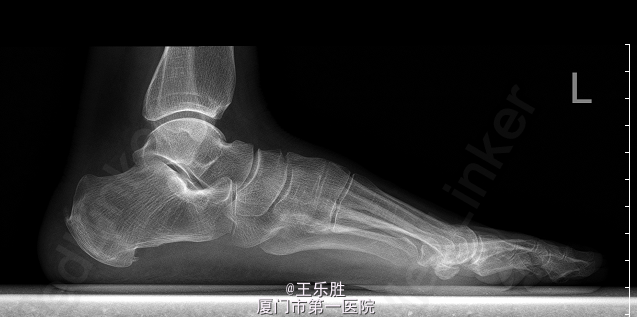

患者,女,58岁,因“左足跟疼痛半年”入院。患者半年前起无明显诱因下出现左足跟疼痛,行走时明显,休息后能缓解.

左足跟轻度肿胀,局部皮肤无红肿及皮温升高,轻压痛,左足背动脉搏动存在,肢端血运感觉正常,足趾活动尚可。MRI提示:“左足跟骨水肿”.

初步诊断:左足跟痛. 行CT(左下肢)检查提示:左跟骨骨折,断端稍嵌插、骨质增生样密度增高,跟骨结节骨质增生。余骨未见明显骨质异常,关节间隙如常.